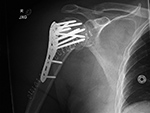

Humerus periarticular locking plate with Vitoss bone graft substitute

Bilateral proximal humerus periarticular locking plates

Periarticular plate

Humerus periarticular locking plate with bone substitute

Right humerus periarticular locking plate

Left humerus periarticular locking plate

57 year-old man with comminuted bilateral proximal humerus fractures. Skin staples are present. There are old, healed rib fractures on the left.